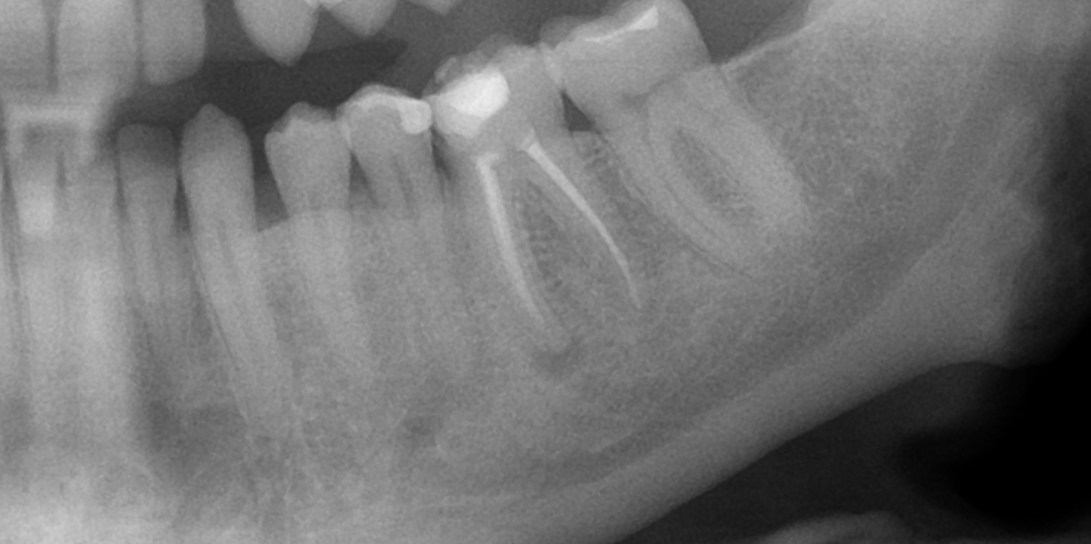

Dantų kanalų gydymas